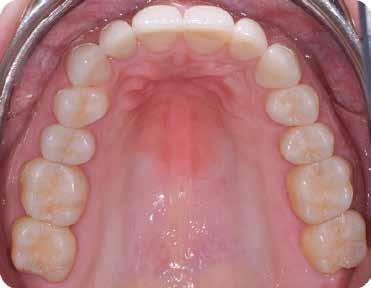

ezen a területen, a fogászat profitál az ilyen fejlesztésekből, és ma már számos kezelési megoldást kínálunk pácienseinknek. Rezidens korom alatt klinikai szakfelügyelőként dolgoztam akadémiai környezetben, ahol elsősorban kivehető fogpótlásra szoruló geriátriai betegeket kezeltem, valamint olyanokat, akiknek fix fogpótlásra, például fog- vagy implantátummal ellátott hagyományos rögzített fogpótlásra (azaz korona és híd) volt szükségük, elsősorban arany vagy fémkerámia felhasználásával. Az ezekben az években megfigyelt klinikai kudarcok és a beavatkozások invazív jellege, nevezetesen a foghúzásra vonatkozó több fúrás és egyszerűbb döntések jelentős szerepet játszottak a kutatási irányvonalam kialakításában az évek során. Ez volt az az időszak is, amikor elkezdtem többet foglalkozni az adhezív fogászattal, ami megváltoztatta a protetikai fogászat klasszikus arculatát, és határozottan kevésbé invazívvá tette azt (1. a-d ábrák). Ma, az intenzív transzlációs és klinikai kutatás eredményeként, különös tekintettel a fogászati bioanyagok alkalmazására, klinikai szakértelmem a minimálisan invazív, adhezív eljárások alkalmazására összpontosít a protetikai fogászatban, a szövődmények kezelésére és a költséghatékony kezelési lehetőségek felkínálására.

1. a-d ábrák: a) Fogerózió a molárisok okkluzális felszínén, b) maratás foszforsavval, c) minimálisan invazív műgyanta-kompozit fedőréteg levegővel történő felszívása, d) adhezív ragasztott fedőréteg a hiányzó zománc és dentin helyreállítására.